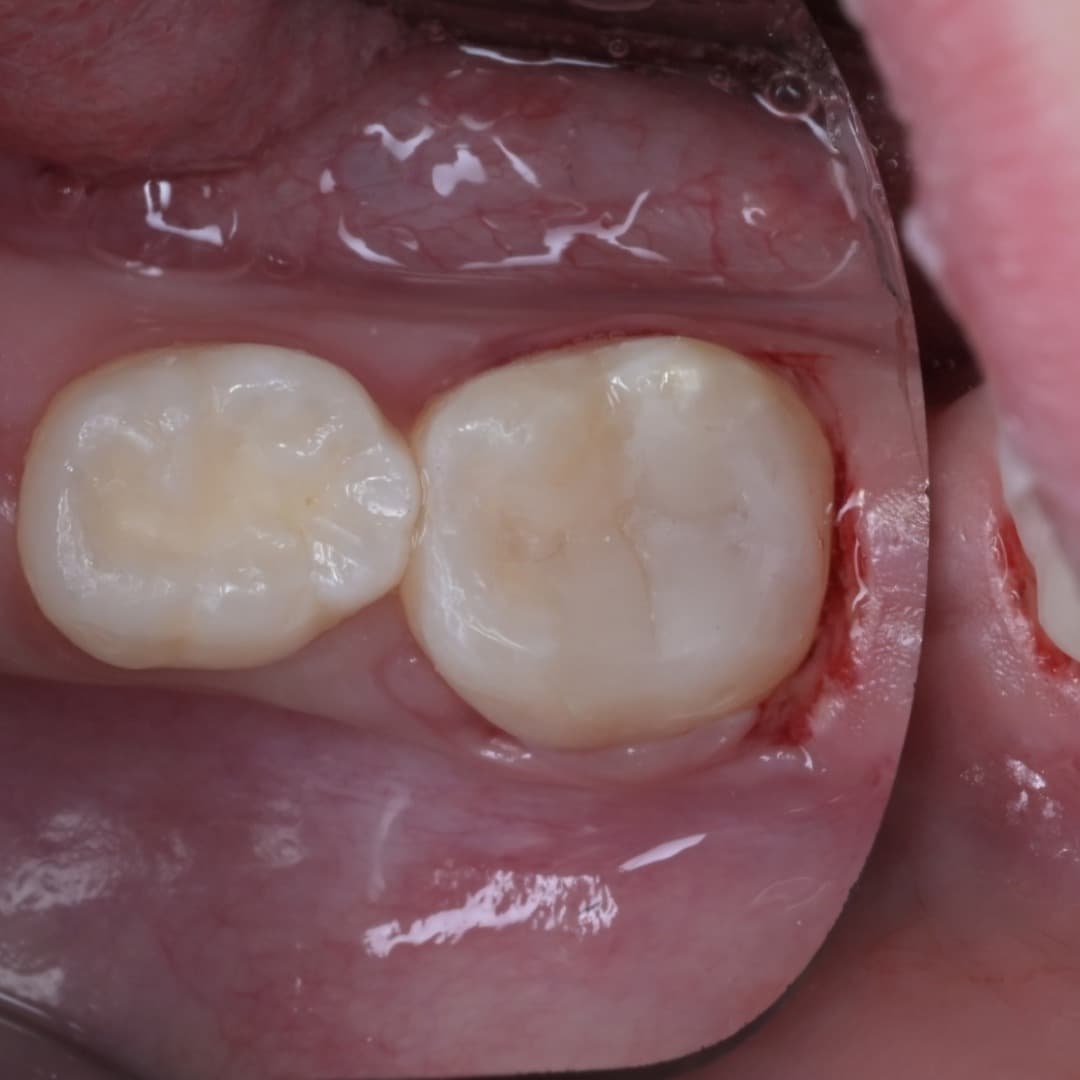

레진빌드업 · 2026.04.23

레진빌드업

2차우식이 생긴 인레이 수복물을 레진빌드업으로 재치료